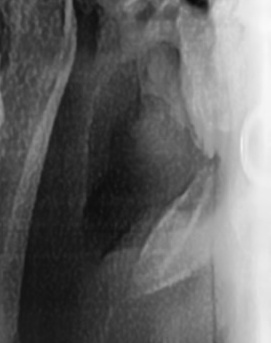

어금니 뒤 잇몸 부음 우선 원인부터 살펴보면 이러한 증상은 단순한 잇몸 염증에서부터 더 심각한 치주 질환이나 사랑니 문제까지 다양하게 발생할 수 있는데요. 보통 잇몸이 붓는 것은 세균 감염, 음식물 잔여물에 의한 자극, 치주 질환, 사랑니 문제 등이 원인이 되는 경우가 많으며 증상이 가벼울 때는 자연적으로 가라앉을 수도 있지만, 제대로 치료하지 않고 반복되는 잇몸 문제가 갈수록 진행된다면 염증이 심해지고 통증이 심해질 수 있고 잇몸이 주저 앉거나 심한 경우 치아가 흔들릴 수 있어서 원인을 정확하게 파악하고 적절한 치료를 받는 것이 중요하다고 볼 수 있어요

어금니 뒤 잇몸 부음의 문제는 사랑니가 원인이 되는 경우도 많은데 사랑니는 특히 현대인들의 경우 제대로 나오지 못하고 매복되는 경우가 많으며 완전히 나오지 않은 사랑니는 잇몸 속에서 자라면서 주변 잇몸을 자극할 수 있고, 일부만 노출되면 음식물이 끼면서 염증이 생기기도 하며 특히 어금니 뒤쪽 잇몸이 붓고 지속적으로 불편함을 느낀다면 사랑니로 인한 염증을 의심해 볼 수 있어요. 사랑니로 인한 문제의 경우 단순한 소염제나 구강 세정제로 해결되지 않고, 사랑니를 발치해야 잇몸 염증이 해결되는 경우가 많이 있어요

결론적으로는 통증이 심하거나 염증이 오래 지속되는 경우에는 치과를 방문해서 정확한 진단을 받는 것이 중요한데 단순한 잇몸 염증이라면 치석 제거와 항생제 치료로 호전될 수 있지만, 치주염이 진행된 경우라면 보다 적극적인 치료가 필요할 수 있어요. 만약 사랑니로 인해 잇몸이 자꾸 붓는다면 사랑니 발치를 고려해야 하겠고 사랑니가 완전히 매복되어 있다면 수술적인 방법으로 제거해야 할 수도 있어요. 특히 반복적으로 붓는다면 사랑니 검사를 받아보거나, 치과에서 정밀 검진을 통해 치주 상태를 확인하는 것이 필요하다는 점에서 어금니 근처의 잇몸이 반복적으로 불편하다면 꼭 치과를 찾아보시길 바라고 있어요